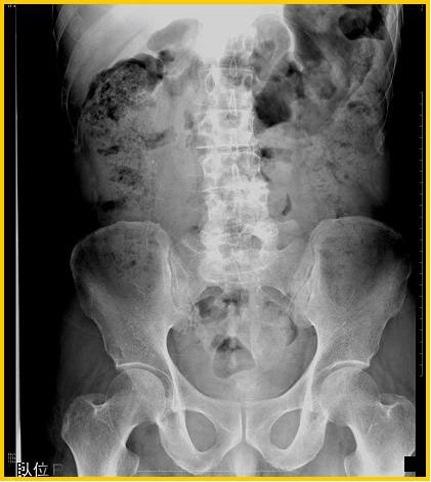

疾病(病理主体)的分类炎症性・溃疡性疾患/静脉硬化性大肠炎

部位(按器官分)大肠/占据大肠的2个以上区域

检查方法X线